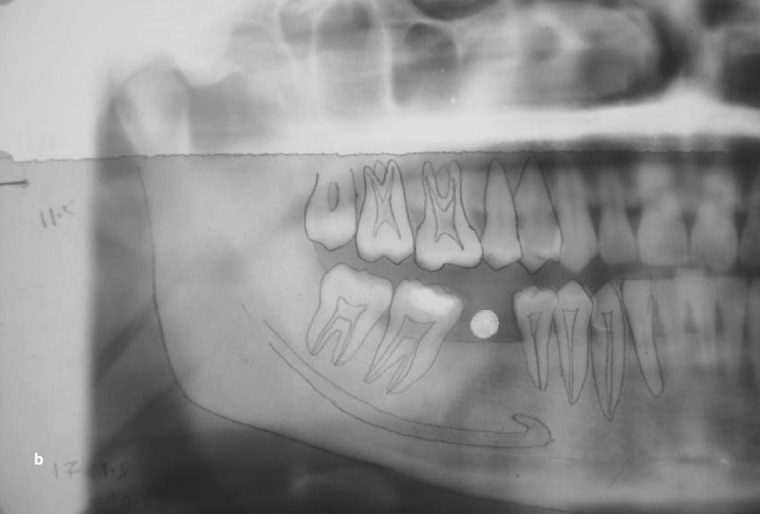

Diagnostic OPG